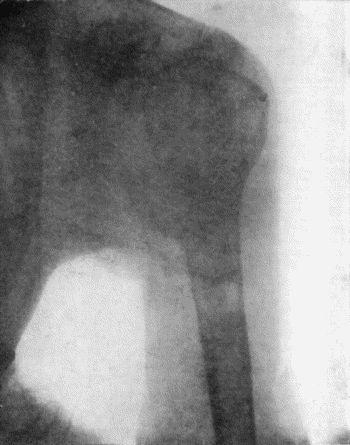

71.Radiogram of Aneurysm of Aorta 303

145.Radiogram of Myeloma of Humerus 492